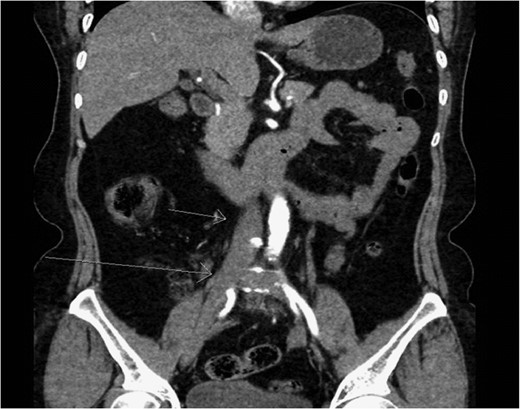

On CT and ultrasound imaging of the abdomen, the patient was found to have an anomalous venous connection between the left and right saphenous veins. The connection traversed across the anterior abdominal wall and contained an aneurysmal segment close to the right saphenofemoral junction that was 3.6 cm in diameter and was partially thrombosed (Figs 1 and 2). The patient had a duplex ultrasound on hospital day one that showed the femoral veins to be patent bilaterally. Systemic anticoagulation was started with warfarin. On hospital Day 2, the patient’s pain improved and she was subsequently discharged on warfarin therapy before her INR was therapeutic with an outpatient lower extremity venous duplex to ensure no further progagation of the thrombus.

Coronal section of CTA of the abdomen/pelvis capturing the anomalous connection between the left and right greater saphenous veins with an aneurysm near the right saphenofemoral junction. Short arrows pointing up shows the tortuous connection of the greater saphenous veins. Long arrow pointing down demonstrates an aneurysm in the anomalous saphenous vein connection.